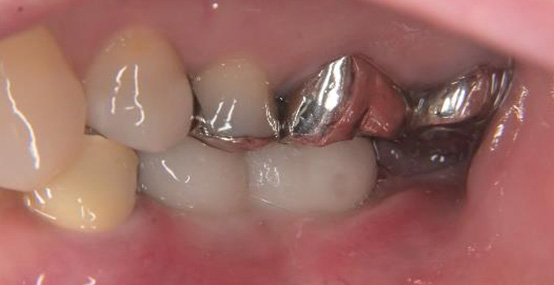

被せものの比較(左が術前、右が術後の写真です)

被せものの比較(上が術前、下が術後の写真です)

インプラントの植立位置を工夫することによって左下の被せものの厚みが確保され、被せものが割れにくい構造にすることができました。

術前の被せものの厚みが薄いという問題点も骨の高さ及びインプラント体を入れる深さを調整することにより十分な被せものの厚みが確保できています。